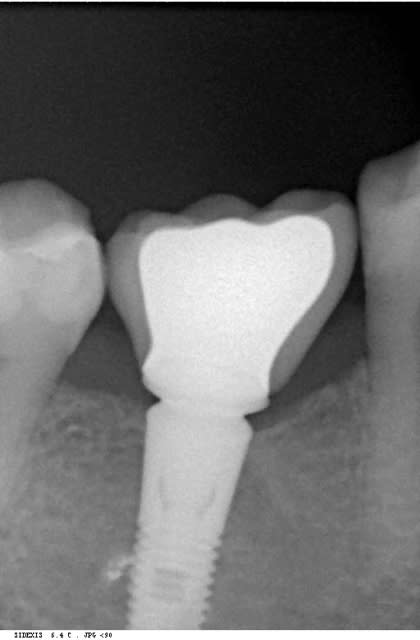

bon les pièces jointes d'alhoun.

décidément aussi nul en endo qu'en internet, et ton implant il est de traviole;)

Trev5 lavbuq - Eugenol

Trev1 rgpu7x - Eugenol

Trev2 c5sddm - Eugenol

Trev3 wgcbda - Eugenol

Ok j'ai compris. Par contre, sur la radio l'implant a l'air d'être conique sur toute sa hauteur, c'est une illusion d'optique où il est vraiment comme ça, je ne le vois pas sur le site d'Astra ?

tu parles de celui de growler?

c'est normal c'est pas un astra, c'est un easy implant, mais il est pas conique tout le long il me semble.

çà doit être une déformation du cliché, regardes bien le premier cliché avec le pilier de cicatisation: on voit bien la partie cylindrique puis l'évasement.